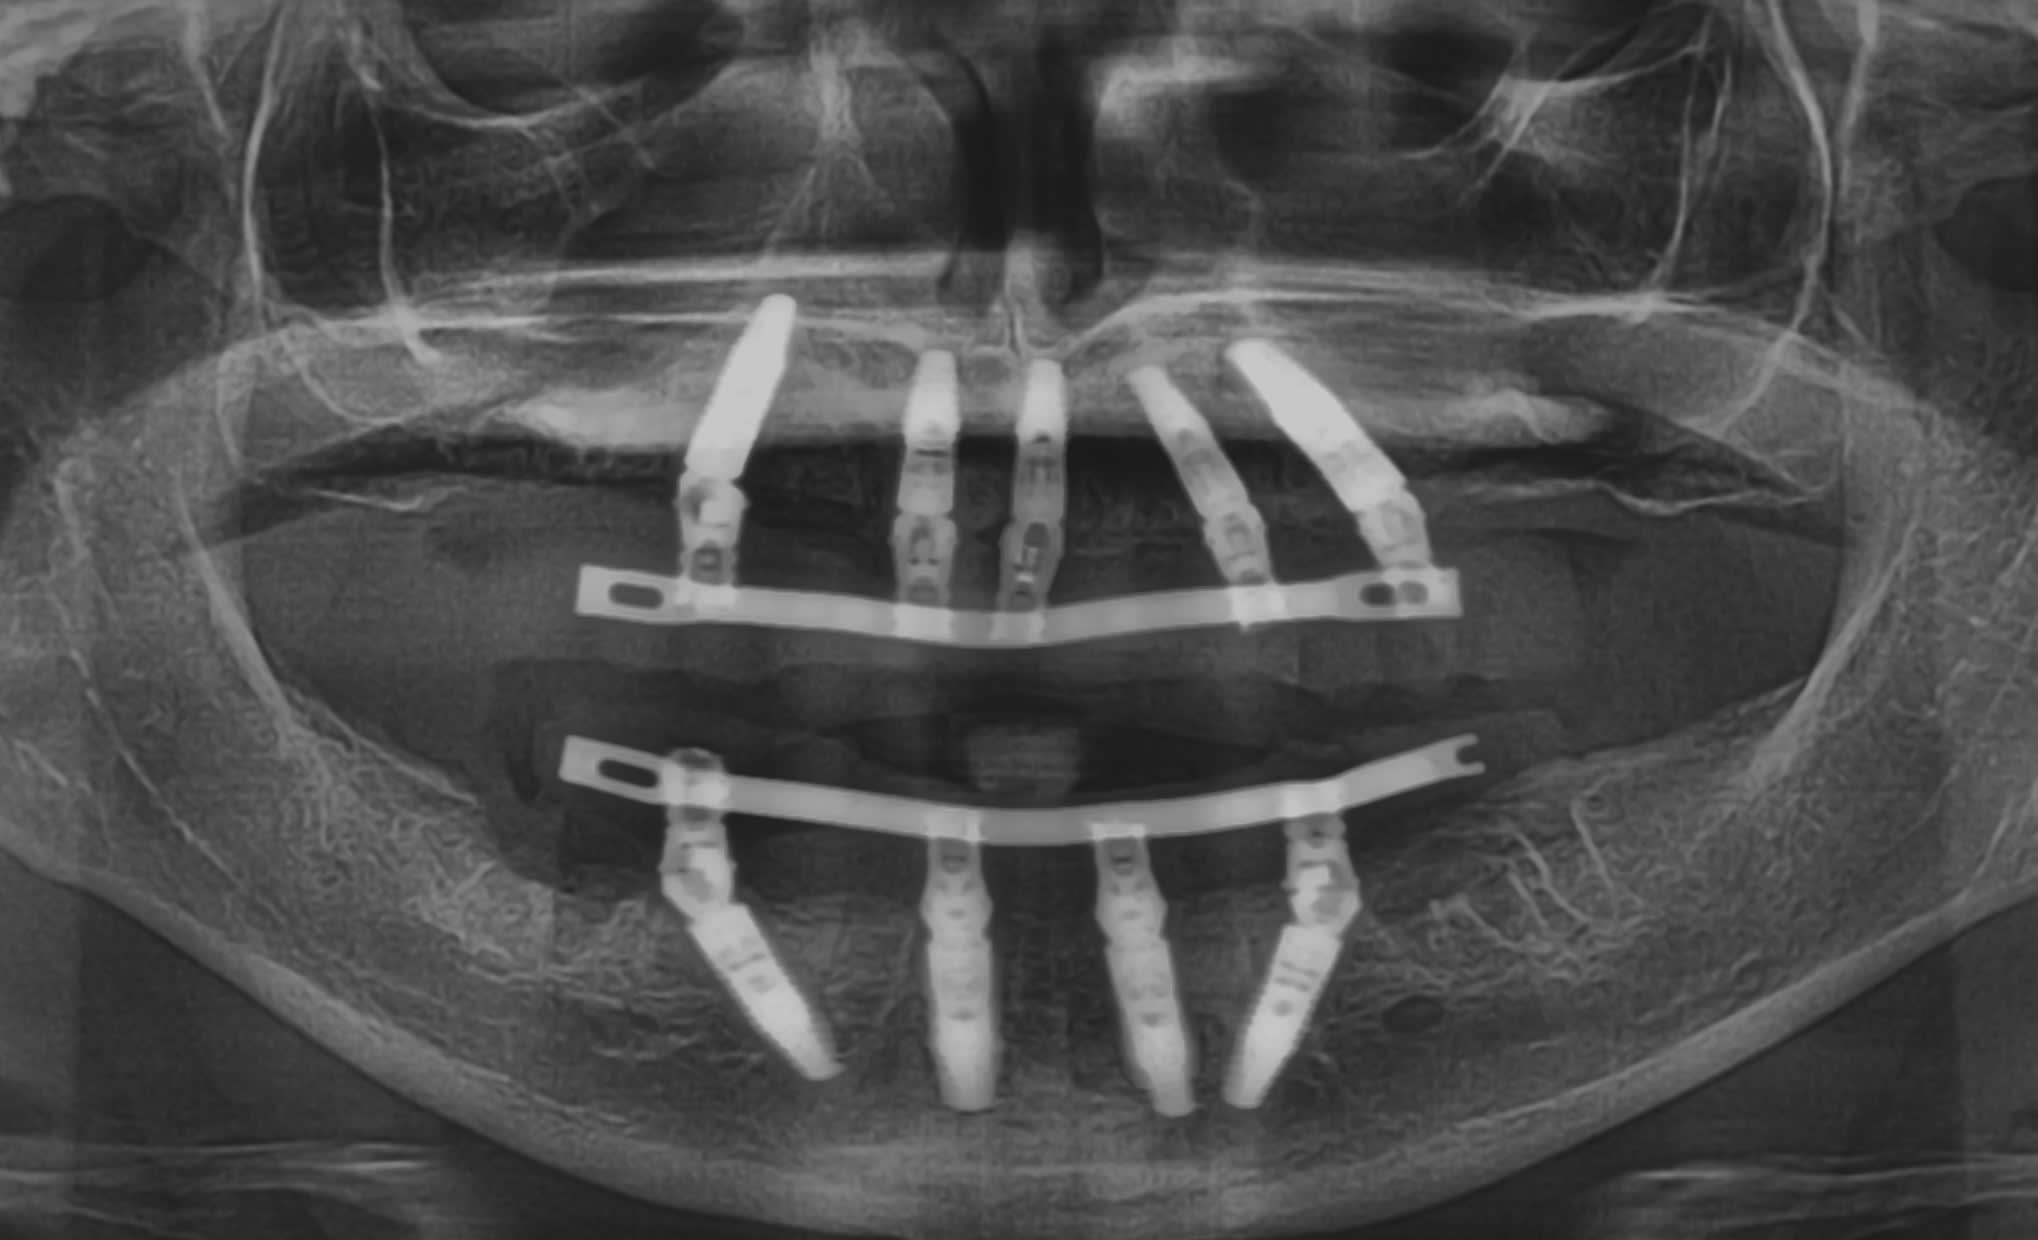

The implant sites were prepared for the Straumann BLT implants (except for bone tapping) using the manufacturer’s protocol.14,15 The implants were placed using the surgical guide template for sites Nos. 4, 7, 8-9, 11, 13, 21, 23, and 26 with insertion torques measured at 35 Ncm; No. 28 recorded a 20-Ncm insertion torque value. All implants were 4.1 mm in diameter and 14 mm in length except for Nos. 7, 8-9, and 11, which were 12 mm in length (Figure 7). All 17- and 30-degree-angled implants were bone-profiled prior to screw-retained abutment placement. This allowed the complete seating of the screw-retained abutment at the recommended 35 Ncm torque. Using the available Straumann bone profilers with the appropriate Regular Connection (RC) inserts was a critical step for correct abutment fit. The following screw-retained abutments (all were 2.5-mm gingival heights) were then chosen: straight for Nos. 23 and 26; 17 degrees for Nos. 4, 7, and 8-9; 30 degrees for Nos. 11, 13, 21, and 28. Tall protective healing caps were then placed (Figure 8), and the dentures were evaluated to ensure there was adequate space for the pink acrylic to allow for bite registration material thickness.

The next afternoon, the prostheses were inserted (Figure 10) and panoramic radiographic confirmation of proper seating was obtained (Figure 11). Any necessary occlusal adjustments were then completed. The patient was given written instructions to be on a very soft diet for the first 4 weeks, after which a normal diet could resume. The patient was then seen every 2 to 3 weeks for deplaquing and plaque control review, per the protocol outlined earlier. The occlusion was also refined as needed. The patient was given a water irrigation device and reviewed at 6 weeks post-surgery.